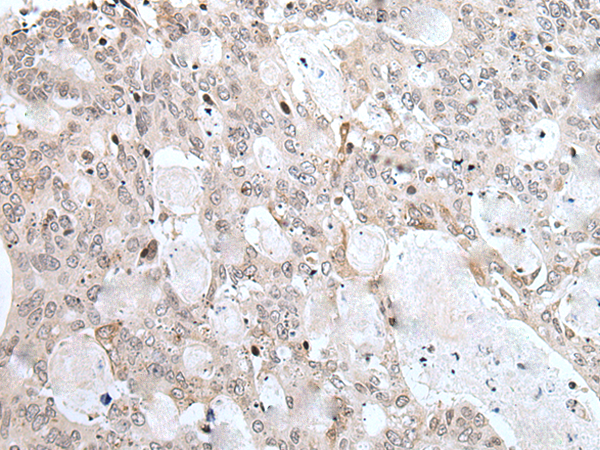

分类: 科研抗体货号: P12830别名: F3; GP135; MYPCN应用: WB,IHC反应种属: Human, Mouse, Rat